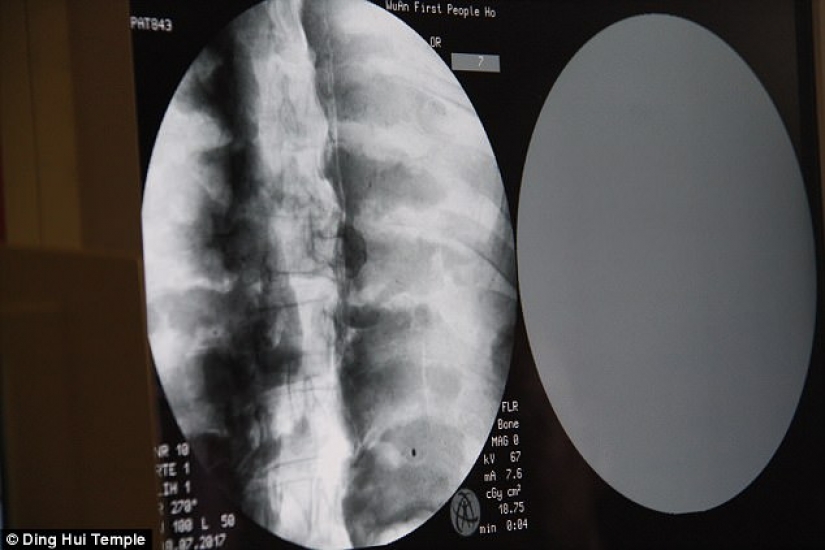

Por Pictolic https://www.pictolic.com/es/article/una-momia-milenaria-de-un-monje-budista-tiene-un-cerebro-y-un-esqueleto-preservados-en-perfecto-estado.htmlEl cuerpo momificado de un monje budista de mil años todavía tiene los huesos y el cerebro intactos. Esto fue revelado por una tomografía computarizada.

La tomografía computarizada se realizó el 8 de julio. La gente se sorprendió cuando los médicos dijeron que el esqueleto y el cerebro de Ci Xian estaban en perfectas condiciones. "Podemos ver que sus huesos están tan sanos como los de una persona normal: la mandíbula superior, los dientes superiores, las costillas, la columna vertebral y todas las articulaciones están perfectamente conservadas. Esto es increíble", dijo el Dr. Wu Yongqing.